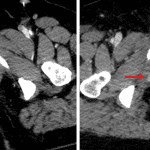

- Multifocal pelvic hematomas with an area of contrast density adjacent to the right inferior pubic ramus fracture which increases in size on delayed phase images

- Pelvic trauma with active hemorrhage

Extensive pelvic trauma including right obturator ring fractures, left sacral fractures, and avulsion of the abdominal musculature from the right iliac crest with multifocal associated hematomas and evidence of active hemorrhage adjacent to the right inferior pubic ramus fracture.